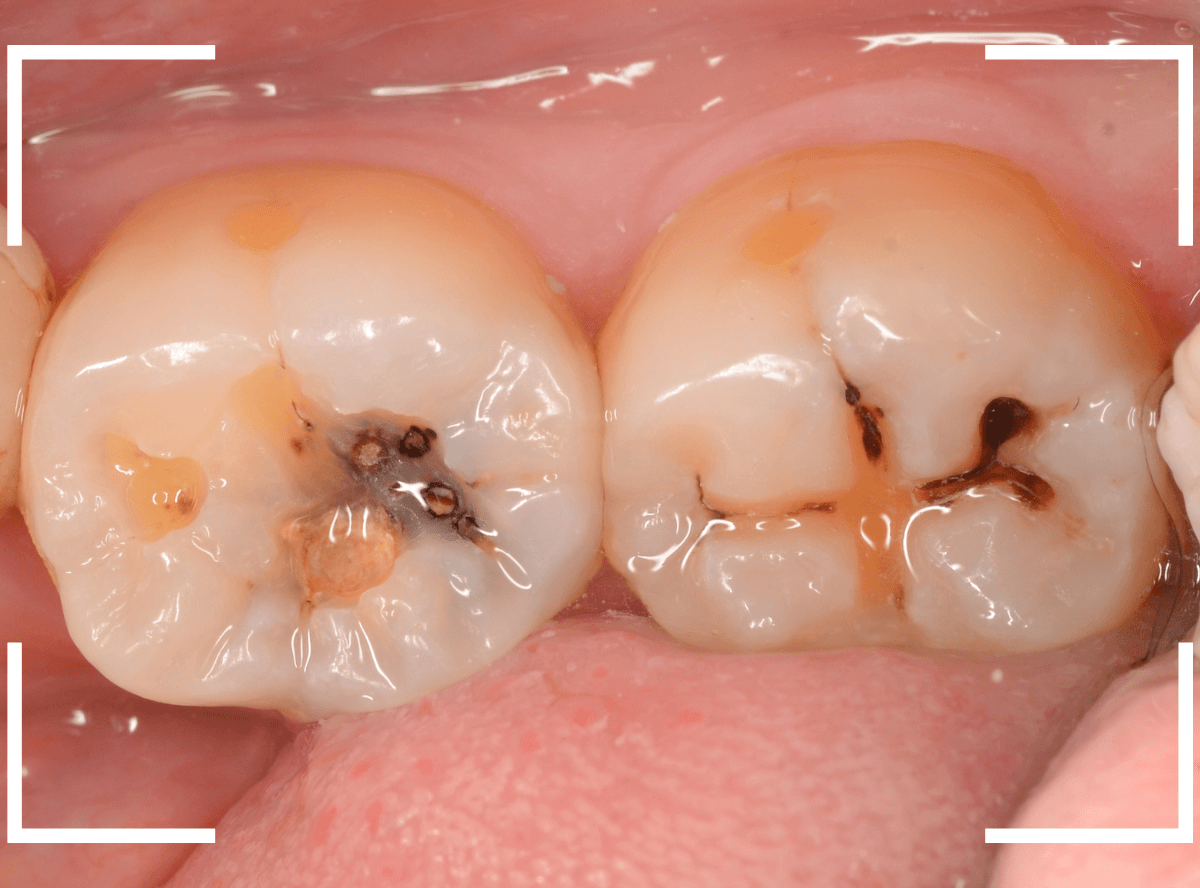

Case.2 レントゲンで判別しづらい、小窩裂溝う蝕

今回は、レントゲン写真で判別しづらい、小窩裂溝う蝕です。

写真では、2本の歯とも、歯の溝に虫歯が出来ているのが確認できます。

レントゲン写真で確認します。

〇部が虫歯の部分です。

左側の歯はうっすらと黒い影が見えますが、わかりづらい写り方です。

虫歯の部分を少しずつ削りながら、虫歯を確認します。

左側の歯はかなり虫歯が広がっているのがわかりますね。

典型的な、内部で広がる小窩裂溝う蝕です。

両歯とも、虫歯を全て除去したところです。

歯の溝から、かなり虫歯が広がっている状態でした。